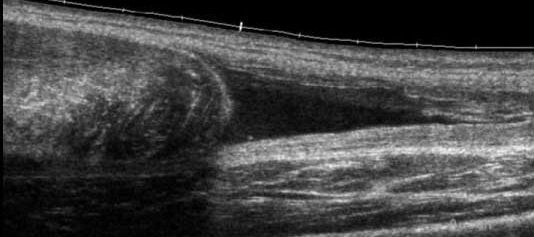

Echivalentul stadiului IV al lui Rodineau se caracterizeaza prin existenta unei rupturi sau unei dezinsertii musculo-aponevrotice complete cu,cel mai frecvent fascicol muscular retractat flotant intr-o cavitate hematica

Stadiul IV Rodineau – ruptura la jonctiune mio tendinoasa

Muschi retractat flotant in colectie hematica

Echivalentul stadiului IV al lui Rodineau se caracterizeaza prin existenta unei rupturi sau unei dezinsertii musculo-aponevrotice complete cu,cel mai frecvent fascicol muscular retractat flotant intr-o cavitate hematica Exista in aceste echivalente ale stadiului IV un caz particular, reprezentat de o ruptura osteotendinoasa (traumatismul spinei iliace antero-inferioare in leziunile dreptului femural la fotbalisti de exemplu